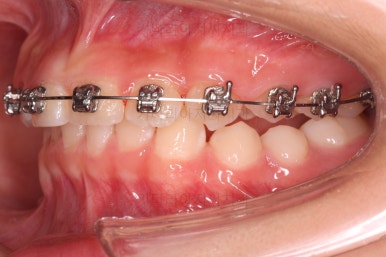

우선 윗니에만 교정장치를 부착했습니다.

성장치료라더니 교정치료? 하실 수 있지만 윗니를 가지런하게 해준 이유는 아래턱을 앞으로 성장시켜줄려니 윗니 앞니가 옥니처럼 가로막고 있어서 아래턱이 앞으로 나올래야 나올 수 없는 상황이었어요.

그래서 앞니의 각도를 먼저 개선해주기로 했죠.

앞니의 각도가 앞으로 살아난 것이 보이실 거에요.

자연스레 과개교합 경향도 개선되어 어금니로 물렸을 때 아래 앞니가 점점 보이기 시작해요.

아랫니도 바로 교정장치를 부착하고, 교정장치를 통해 윗니~아랫니를 끌어주고 철사를 이리저리 디자인해서 힘을 주고, 다양한 부가적인 부착물들을 활용하기로 했어요.

어떤 장치가 중간중간 활용되고 있는지는 틀린그림찾기처럼 찾아보시길 바랍니다.ㅎㅎ

과개교합, 옥니, 앵글씨 2급 부정교합 모두 좋아지고 있어요.